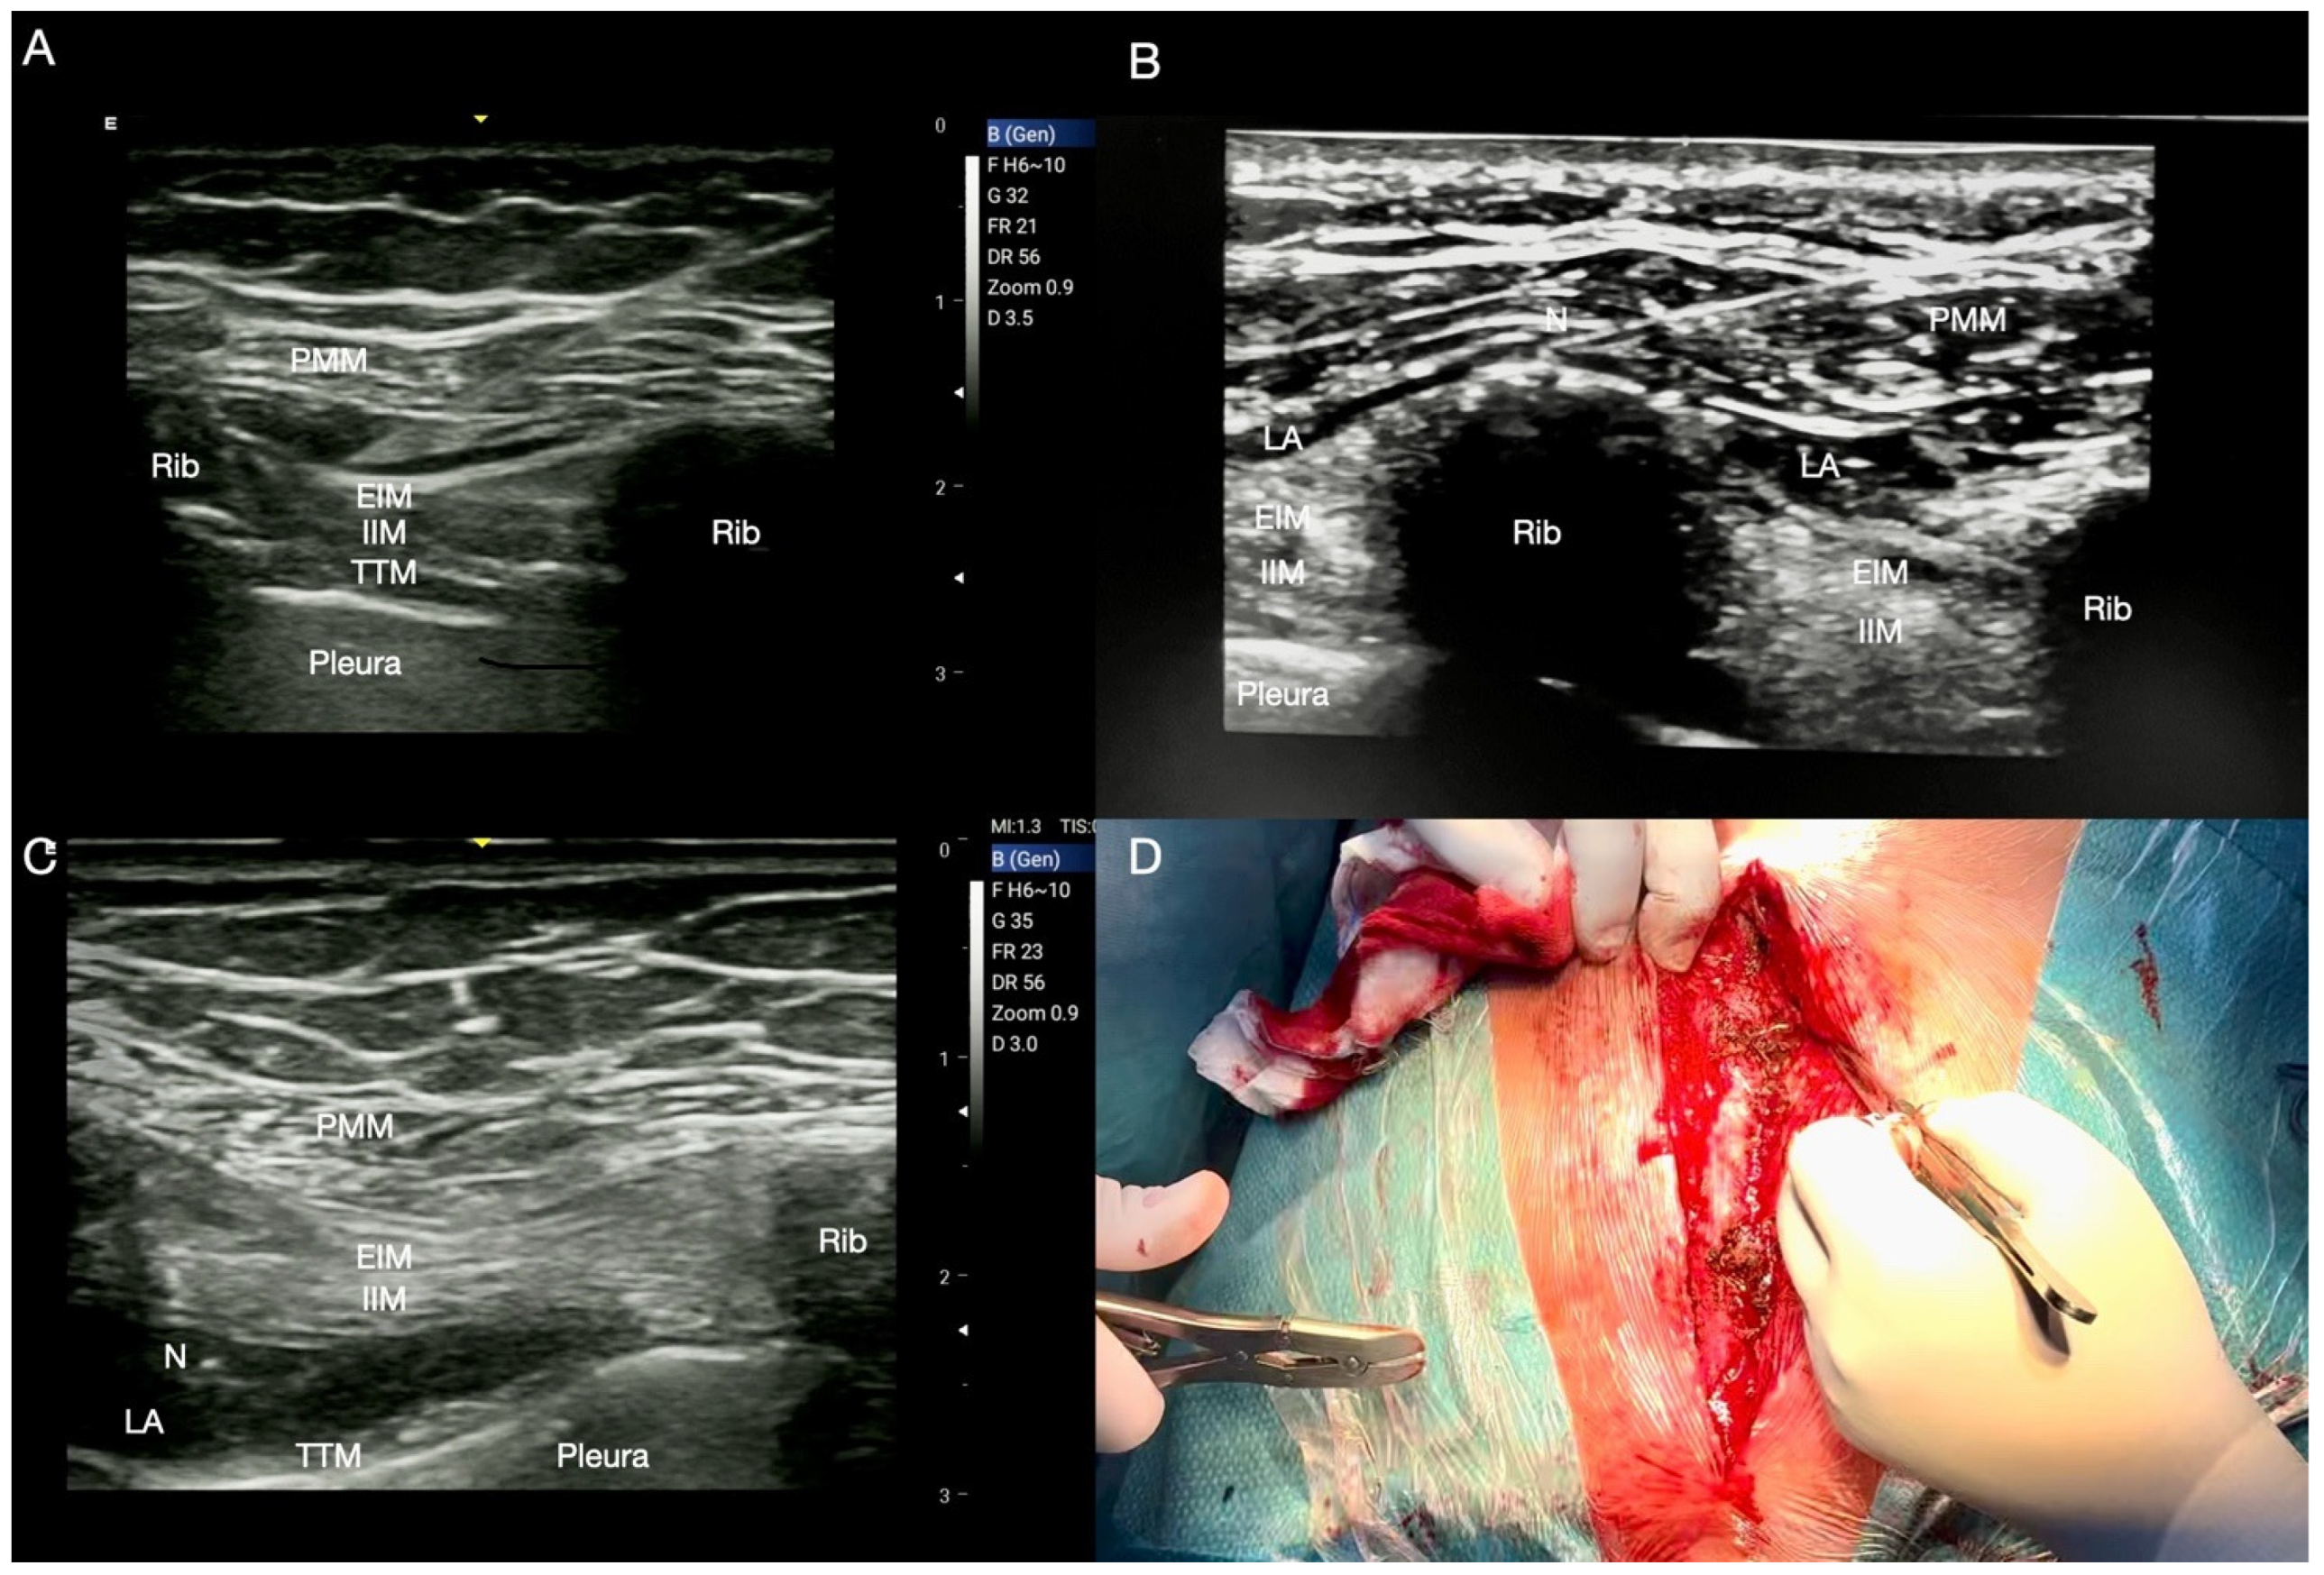

Technique for IPP and PSP

| IPP | Postoperative sternal analgesia, placement of anterior chest drains, post-traumatic chest injuries, ICD or pacemaker implant. | Lateral and medial pectoral nerves. Pectoral muscles. Anterior thoracic wall. Between pectoralis major and minor muscles. 10 mL of LA. | The lateral to medial approach allows a more comfortable position than the medial to lateral one. The pectoral branch of the thoraco-acromial artery is an important landmark to identify the inter-fascial plane. An effective block is realized when the ultrasound “double V” sign is visualized. |

| PSP | Pain management after thoracotomy in association with SAP block. | T2–T6 intercostal nerves lateral cutaneous branches. Lateral thoracic wall. Intercosto-brachial, thoracic longus and thoraco-dorsal nerves. 4th rib. 20 mL of LA. | Opposite decubitus to the surgical site; probe placed on the mid-axillary line. At level of 4th rib, the LA can be injected below the plane of serratus muscle realizing a deep SAP block or blocking the branches of intercostal nerves in the middle axillary line. |